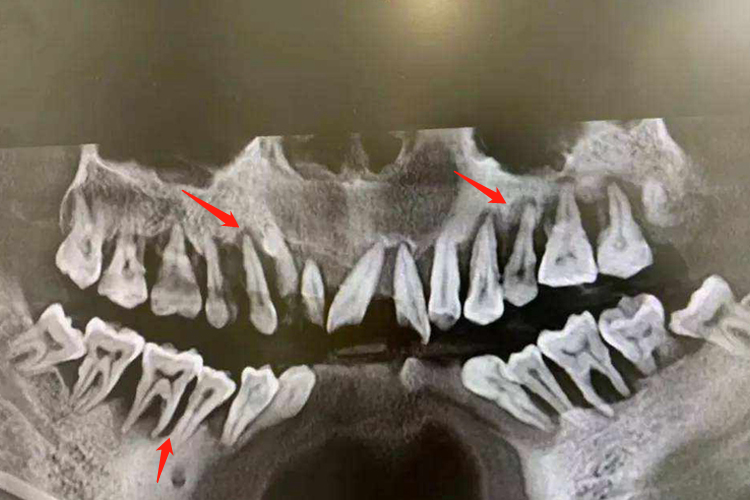

牙槽骨吸收轻重度可通过X线片观察,可见牙齿根尖处高度存在程度不一的下降。

牙槽骨吸收程度可以通过X线片来观察,骨吸收轻度时表现为牙槽嵴顶的硬骨板消失,或嵴顶模糊呈血蚀状。嵴顶的少量吸收使前牙的牙槽间隔由尖变平或凹陷,在后牙则使嵴顶由宽平变凹陷,以后牙槽骨高度降低。牙槽骨重度吸收时,X线片可见根尖区有圆形或椭圆形的骨质疏松投影区,牙槽骨高度下降,严重时可达下降2/3。